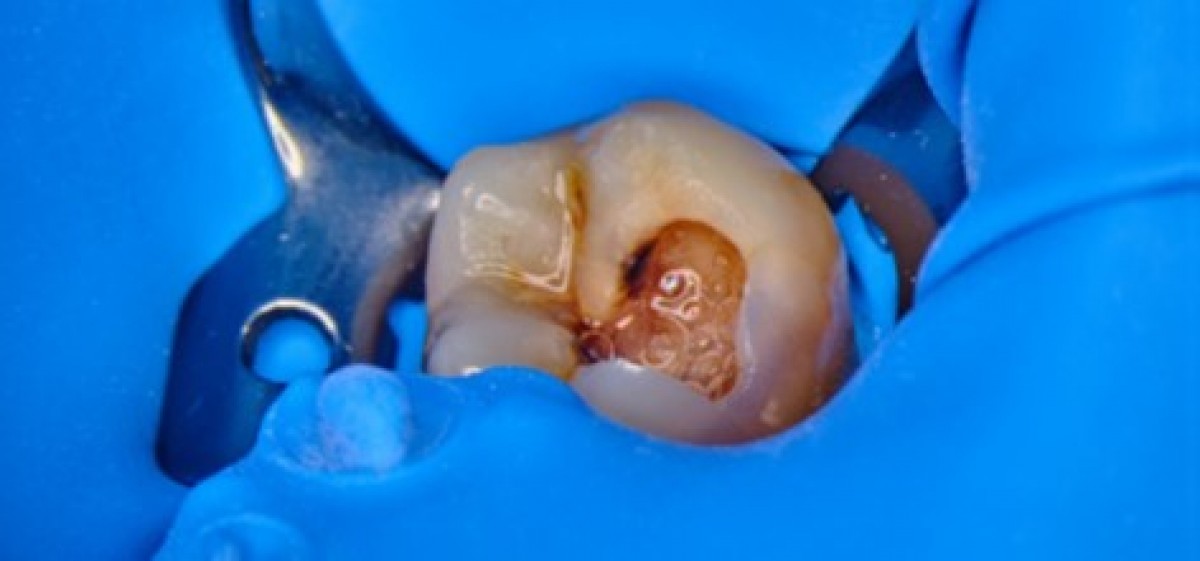

Rubber dam was placed on the tooth in order to isolate the operative field 3 (Fig. 2) and the root canal treatment was began. The first step of a correct shaping of the root canal system is the access cavity 4: it ideally has to be the coronal projection of the root canals and it is meant to be as small as practical. The coronal composite was carefully removed with a diamond-coated bur as soon as the pulp chamber floor was reached (Fig. 3). After designing the access cavity, the carboxy cement that had been placed in the root canals in the primary treatment was removed, and the root canal openings were sought and found with the help of the operative microscope (Fig. 4). Subsequently, it was managed to remove the cement from the root canals. Since the primary treatment had not respected the basic principles of shaping, cleaning and filling tridimensionally the root canal system, it was necessary to consider as the pulp was still present in the root canals. The scouting phase was executed, first with thin stainless steel manual instruments and NiTi rotary files (Fig. 5), then NiTi reciprocating files were used to shape the root canal system 5 (Fig. 6).

A 56 years-old patient came to our office complaining of an intense pain on tooth 3.8. The elements how next ended carious lesion (Fig. 15) and the x-rays confirmed that the decay was in proximity to the pulp chamber (Fig. 16). A lower alveolar nerve block was executed, then rubber dam was placed and the decay was removed with the help of a microscope (Fig. 17-19). After removing all the decayed tissue, the access cavity was completed trying to be extremely conservative and the root canal openings were found and enlarged with the help of ultrasonic tips (Fig. 20). The scouting of the root canal was executed with thin hand files (Fig. 21, 22), then the shaping procedure was carried out by means of reciprocating NiTi files (Fig. 23, 24) 9. The irrigation phase was executed with IrriFlex, a novel polypropylene irrigation tip that has a 2-side vented exits (Fig. 25-27), then the irrigant activation was done with sonic tips. Shaping and irrigation were alternated until the root canals were looking clean and appropriately tapered (Fig. 28-32) 10, 11. Paper cones were then used to dry the root canals (Fig. 33, 34) then, in this case, the obturation was done with single cone and bioceramic sealer (Fig. 35, 36). The access cavity was sealed with composite material, then an indirect restoration was booked.